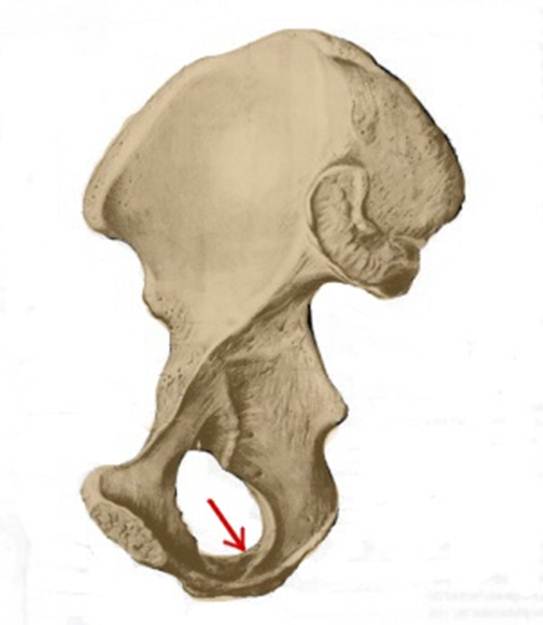

I:

S: Стрелка указывает на os ilium (латинский язык).

S: Стрелка указывает на os ischii (латинский язык).

S: Стрелка указывает на ramus ossis ischii

S:Стрелка указывает на spina iliaca posterior superior

S:Стрелка указывает на lambium internum

S: Стрелка указывает на spina iliaca posterior inferior

S: Стрелка указывает на tuber ischiadicum (латинский язык).

S: Стрелка указывает на foramen obturatum (латинский язык).

S: Стрелка указывает на spina iliaca anterior inferior

S: Стрелка указывает на incisura ischiadica minor

S: Стрелка указывает на incisura ischiadica major

S: Стрелка указывает на spina iliaca anterior superior

S: Стрелка указывает на facies auricularis

S: Стрелка указывает на facies sacropelvica